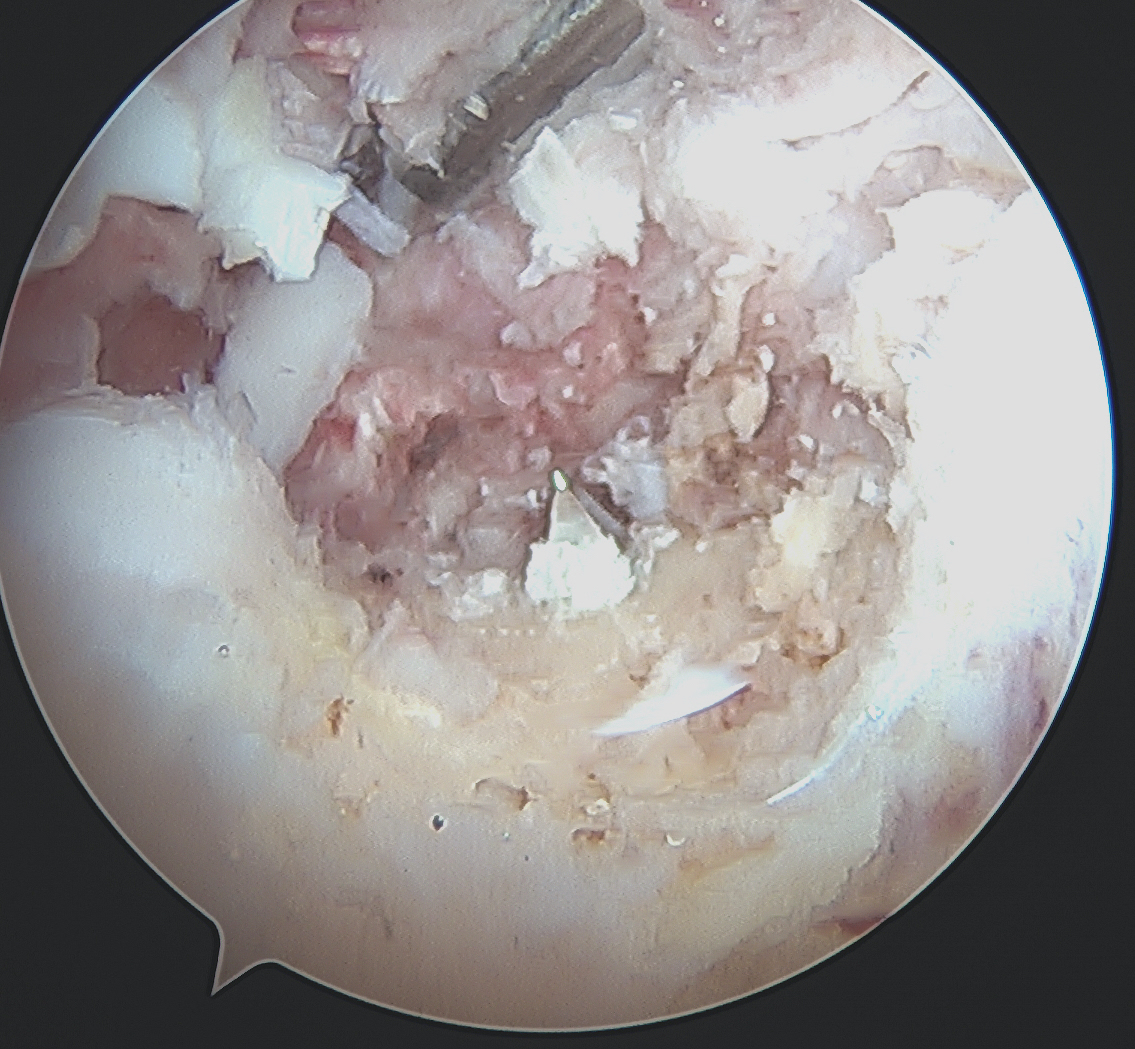

Tibial Tunnel

Incision medial to tibial tuberosity

- PCL jig inserted, usually set at 60 or 65o

- under fluoroscopy, identify the PCL facet

- at least 1 cm below the articular surface

- needs to be more lateral than medial to recreate the anterolateral bundle of PCL

- curette inserted to protect NV bundle

- knee in flexion to protect NV bundle

- beath pin passed

- ream appropriate tunnel (9 or 10 mm for achilles tendon allograft)

PCL tibial tunnelPCL DrillTibial Tunnel PCL